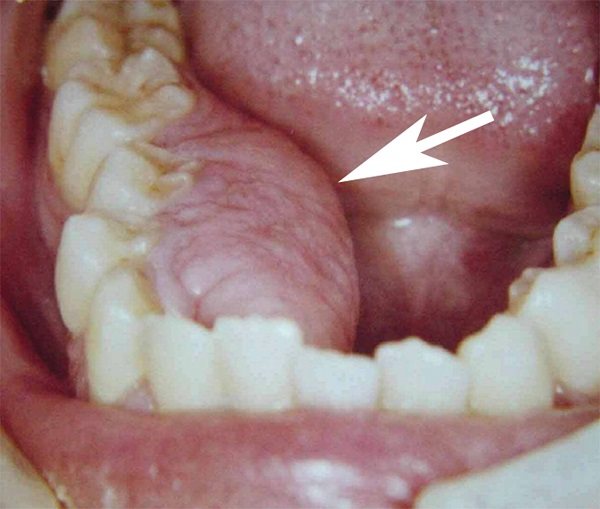

Нарост на десне.

Внешний его вид определяется следующими параметрами:

- Формой – ее сопоставляют с грибом, поскольку у образования отчетливо различается ножка (участок, которым он прикрепляется к десне) и тело (похоже на грибную шляпку).

- Размером – всегда зависит от морфологической и клинической формы, и может варьировать от 2-3 мм (его почти не видно) до нескольких сантиметров.

- Цветом – зависит от разновидности нароста. Так, фиброзный идентичен по окрасу с десной, гигантоклеточная – буро-коричневая или синюшная, ангиоматозный – бывает от ярко-красного до темно-красного. Если его часто травмировать пломбой, зубами, протезными кламмерами, его поверхность сильно изъявляется и изменяет окрас.

- Консистенцией – в зависимости от вида клеток, которые послужили источником его роста, плотность бывает разной: мягкой или твердой.